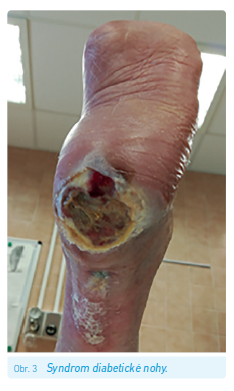

Syndrom diabetické nohy

Syndrom diabetické nohy představuje jednu z pozdních komplikací diabetu. Vzniká spojením řady jiných komplikací – konkrétně diabetické neuropatie a mikro‑ a makroangiopatie postihující dolní končetiny. Zahrnuje diabetické ulcerace (obr. 2), Charcotovu osteoartropatii nebo patologické zlomeniny. Vyskytuje se zhruba u 7 % nemocných s DM.13 Riziko vzniku syndromu diabetické nohy můžeme detekovat pomocí screeningu, který spočívá ve vyšetření hlavních rizikových faktorů – ICHDK (viz níže), diabetické neuropatie (viz výše), vyšetření kožních teplot a zhodnocení kvality obouvání. Podle nalezených změn a fyzikálního vyšetření můžeme následně stratifikovat pacienty a určit u nich míru rizika rozvoje syndromu diabetické nohy a doporučený follow‑up (tab. 2). Ovšem další přístup jak k diagnostice syndromu diabetické nohy, tak zejména k jeho léčbě je jednoznačně multidisciplinární a přesahuje rámec tohoto sdělení.25